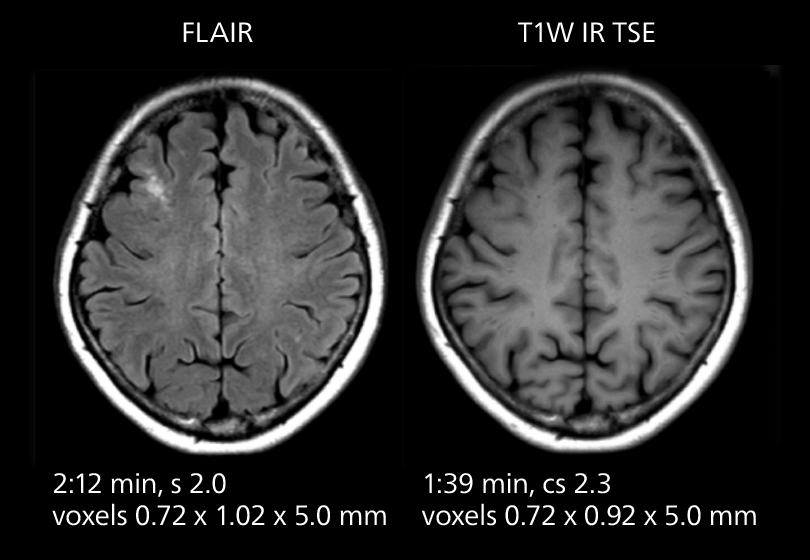

These images of an old cerebral infarction demonstrate the speed and image quality after upgrading to Elition X.

Crisp images are obtained with high resolution and short scan times using Elition X. A cyst can be seen.